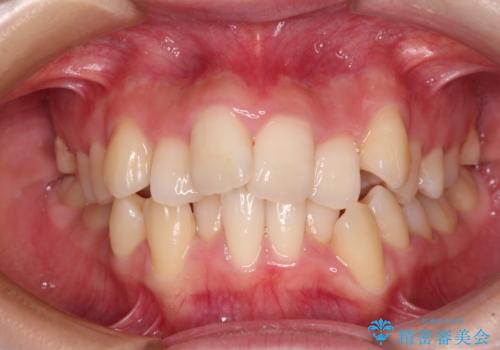

矯正歯科治療 → 上下顎前突(口ゴボ)

- デコボコと口元の突出感を改善 抜歯矯正治療